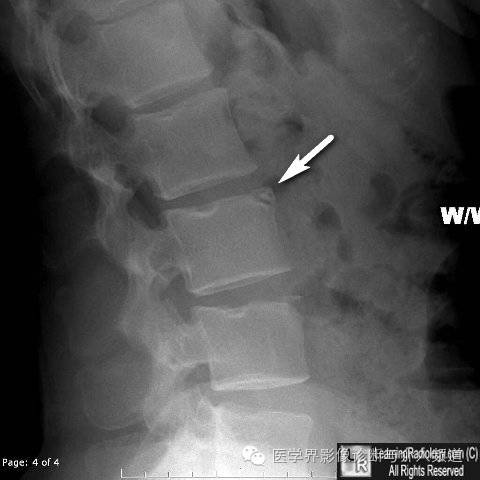

9、椎缘骨: 椎缘骨常见于椎体前上缘,表现为椎体前上角大小不一的三角形骨块,与椎体缺损区相对应,周边硬化。